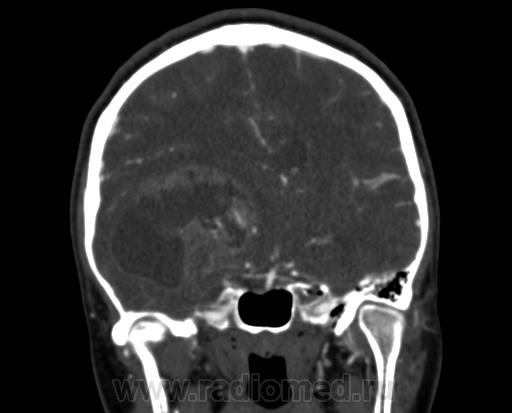

Молодая женщина, 29 лет. Обратилась на прием к неврологу 26.10.12г с  болями в шее, назначено лечение амбулаторно по сосудистой головной боли, остеохондрозу.. После 14.11.12г обратилась к другому неврологу повторно, 16.11.12г направлена в стационар. Жалобы: на снижение зрения, головные боли, головокружения, слабость, повышение температуры. Провели СКТ головного мозга натив и контрастирование. Подскажите пожалуйста, коллеги- Это опухоль? тогда какая (глиобластома, невринома, менингиома?) и локализацию. Спасибо.

Сканы с контрастированием.

Нативное исследование.

Одно можно сказать точно: это не менингиома и не невринома (у тех структура однородная). Это Вам в помощь http://www.radiologyassistant.nl/en/p47f86aa182b3a/brain-tumor-systematic-approach.html

Мне кажется, что тут субэпендимарная глиома. Указываете степень дислокации, накопления и к нейрохирургам.

Согласна с Андреем Юрьевичем. Все остальное возможно, в том числе олигодендроглиома. Впрочем не принципиально. К нейрохирургам!

Только что узнала результаты вскрытия.Гистология пока не готова.

Глиобластома с прорастанием стенки правого бокового желудочка, выраженный отек, смещение срединных структур, вклинение миндалин мозжечка в БЗО.